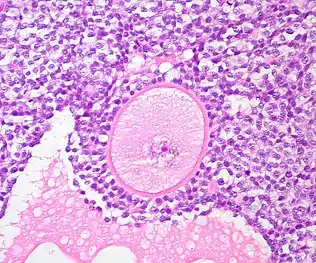

A common source of ovarian tissue used comes from tissue excised from the patient prior to cancer treatment, which is then cryopreserved.[7] The tissue is then cultured to activate the primordial follicles and allow them to develop.[2] To isolate the follicles, a combination of enzymatic and mechanical tissue digestion has shown to be the most effective method to yield a high quantity of follicles whilst maintaining their quality.[8] The enzymes used, liberase DH and DNase, are produced by good manufacturing practice (GMP) to fully comply with GMP guidelines to ensure future application to patients. The enzymatic digestion process is inactivated every 30 minutes and the suspension is filtered to allow fully isolated follicles to be removed and reduce unnecessary enzyme exposure which may lead to damage of their basement membrane and their death.[8]

When recovering the isolated follicles, malignant cells may be inadvertently retrieved, which poses the risk of re-introducing malignant cells into the patient.[8] To minimise the risk of contamination, the isolated follicles undergo a washing step which involves rinsing the follicles with fresh dissecting media, three times, to separate them from surrounding isolated cells.[2][8]